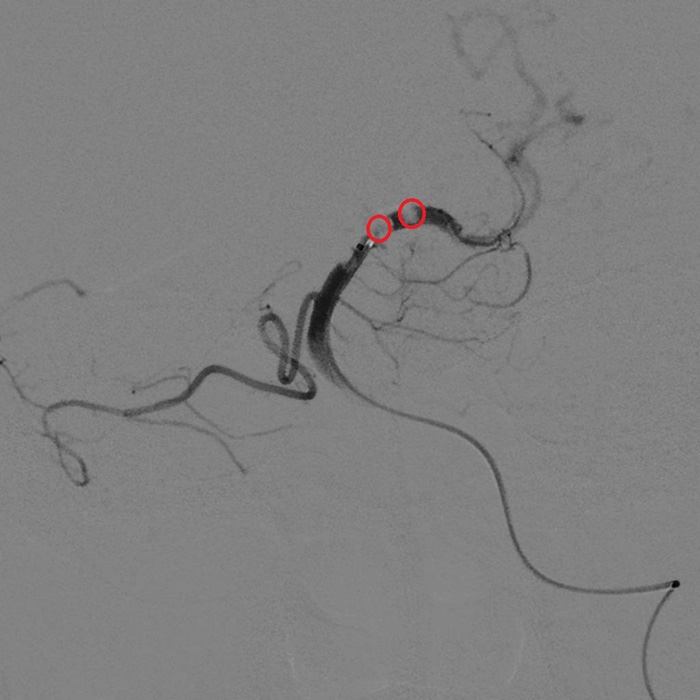

微導(dǎo)管造影顯示血栓(紅圈處)